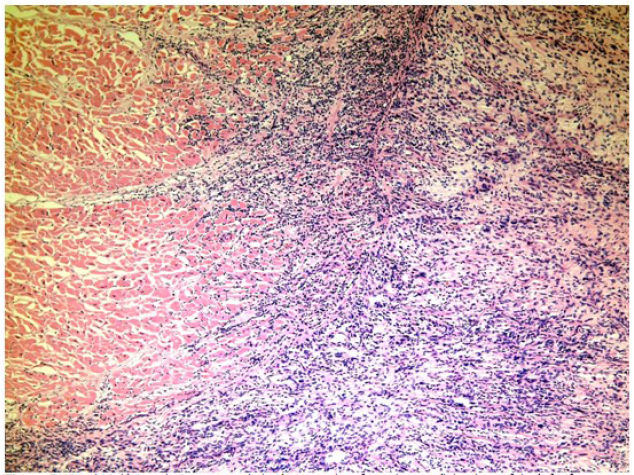

Al examen histológico, con la coloración de hematoxilina-eosina, las células que conformaban la tumoración mostraron aspecto fusocelular, atipia marcada y se precisó su naturaleza infiltrante. (Figura 3).

Se decidió la realización de técnicas de histoquímica útiles en la definición de tejidos conformados por células con morfología celular como lo son el colágeno, el músculo liso y el estriado con vistas a precisar el tejido de origen. Entre estas técnicas se empleó la coloración de van Gieson. (Figura 4)